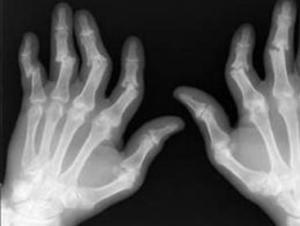

(三)關節影像檢查 X線檢查有助於關節病變的診斷和鑑別診斷,亦能隨訪了解關節病變的演變。是目前最常用的影像學診斷方法,其他尚有關節CT、MRI、同為素等檢查。

(四)關節畸形和功能障礙 指關節喪失其正常的外形和活動範圍受到限制,如膝不能完全伸直,手的掌指關節有尺側偏斜,關節半脫位等。這些